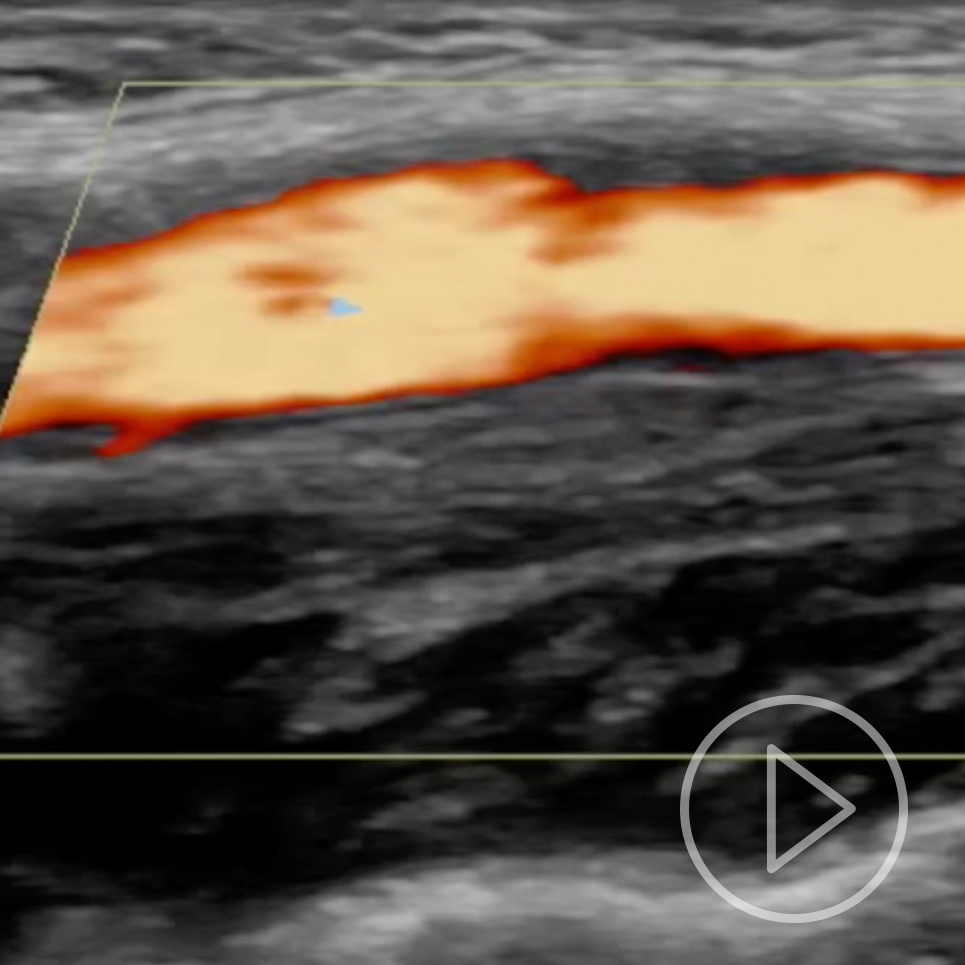

Ved klinisk undersøkelse fant man palpasjonsømhet under høyre bifurkatur. Det var ingen nevrologiske utfall. CT angio av halskar viste intet sikkert patologisk. Derfor ble det gjort ny ultralyd av halskarene, og man fant normalt kaliber av aktuelle carotisbifurkatur. På stillbilder var det vanskelig å se noe galt, men med løpende avbildning så man en isodens fortykkelse i åreveggen som ble oppfattet som en disseksjon. Forandringen var forsvunnet ved ultralydkontroll fire måneder senere, noe som bekreftet diagnosen. MR angio tatt seks uker etter symptomstart viste normale halskar.

Hos denne pasienten var vegghematomet isodenst og vanskelig å se på stillbilder, særlig ved den siste ultralydundersøkelsen (bildet til høyre). Ved den initiale undersøkelsen fremsto det noe tydeligere (bildet til venstre). På videoene kan man se disseksjonen som en veggfortykkelse som beveger seg sammen med karet og ikke med det underliggende vevet.